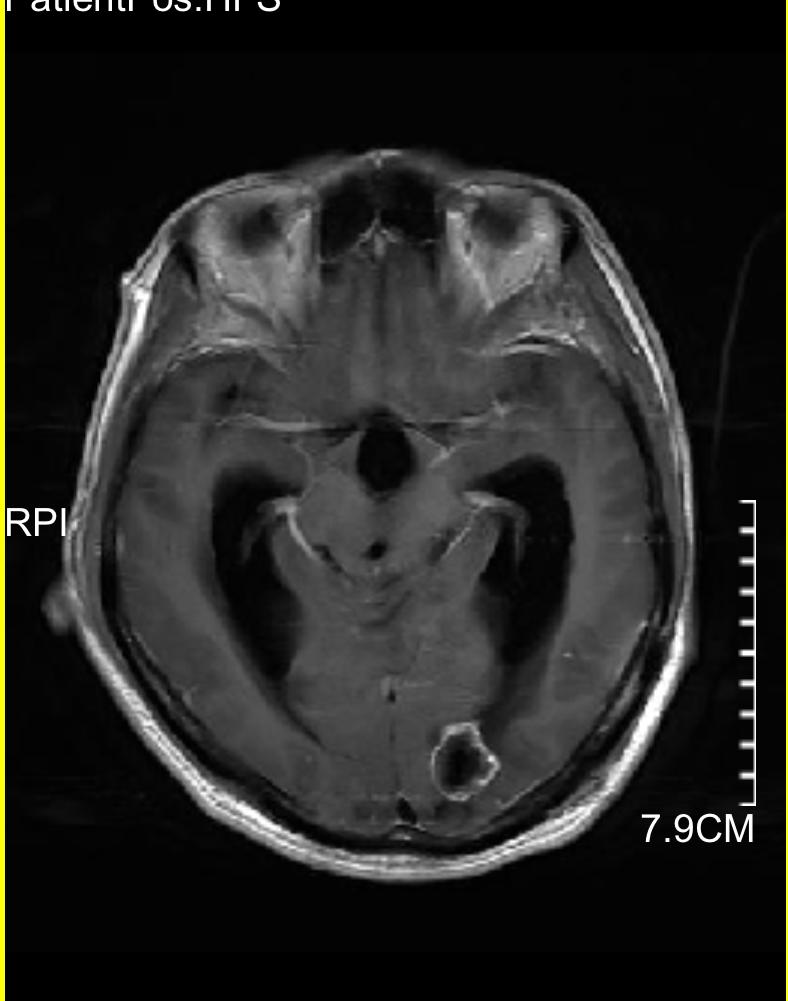

下图的病例是一个以头痛、行走不稳为主要表现,查头颅磁共振发现颅内三个大的转移灶,同时肺部发现巨大肿瘤,脑内病灶给予全部切除,术后根据基因检测结果进行化疗及靶向、免疫治疗。

顶部稍小转移瘤

顶部转移瘤已切除